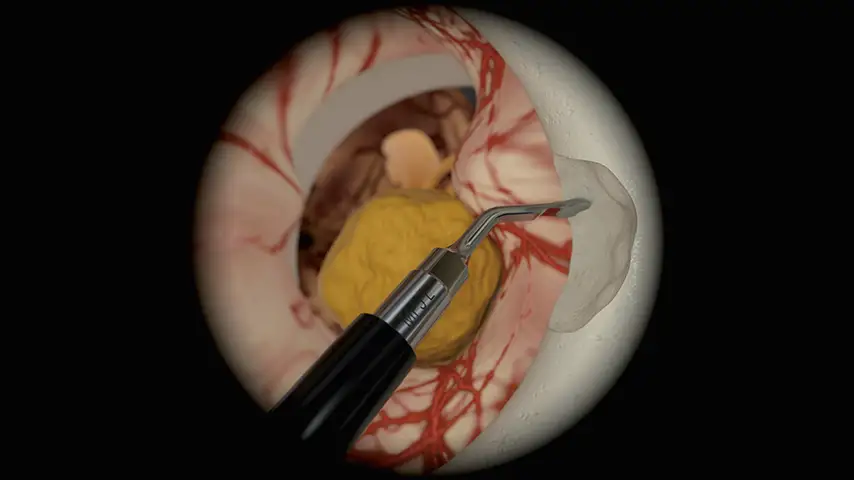

Acoustic nerve decompression

Endoscopic transsphenoidal approach

Selective cut preserves soft tissue. (Dura, neves and vessels)